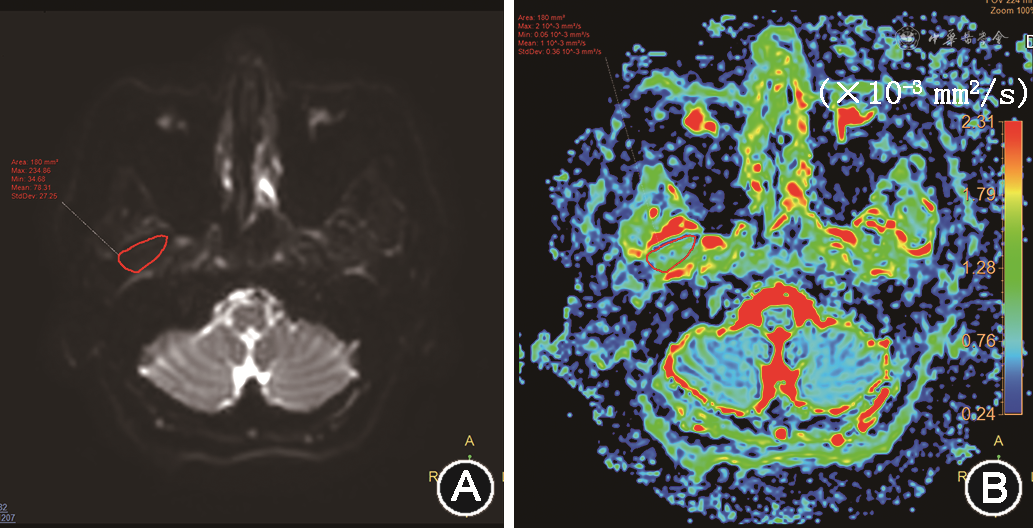

扩散张量成像(diffuse tension imaging,DTI)是一种基于细胞膜和亚细胞结构对水分子扩散的限制,通过测量3个正交方向的水分子扩散强度映射出生物组织水分子在体内扩散特性的功能MRI成像技术,可同时无创评估翼外肌形态和功能改变[19],其表观扩散系数(apparent diffusion coefficient,ADC)见图7,与本征值增加与TMD关节盘移位严重程度接近线性关系,提示微观结构发生病理改变,也意味着DTI扩散参数可作为评估翼外肌功能亢进严重程度的一个指标[20]。